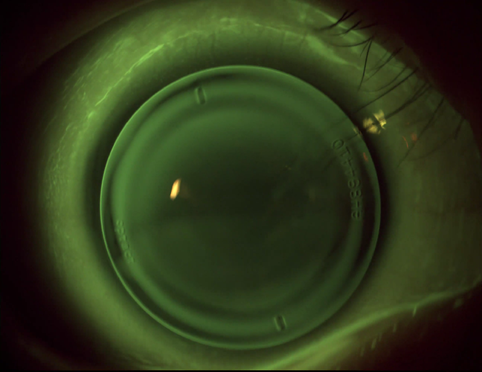

右眼原始地形图

该患者角膜形态较不规则,角膜散光范围居中,角膜散光数值较小。

到片荧光图(2024.8):整体配适可,活动度适中,定位居中。

片上地形图(2024.8.21):离焦光学区小,片上离焦量可高达+20D以上。